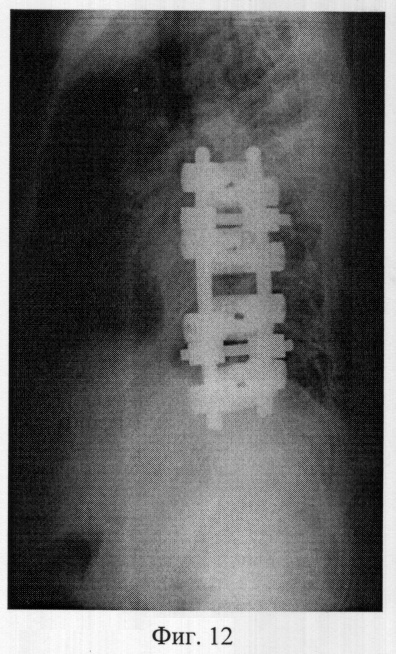

Фиг.12 – рентгенограмма в боковой проекции позвоночника больной X. после операции вентральной коррекции центрального угла деформации и фиксации из переднего доступа.

Пример 3. Больная X., 11 лет, 08.07.05 поступила в отдел новых технологий в вертебрологии и нейрохирургии СарНИИТО по поводу диспластического прогрессирующего нестабильного правостороннего грудопоясничного сколиоза III степени.

В СарНИИТО ей были выполнена рентгенография в стандартных проекциях: фасная (фиг.9) и боковая (фиг.10) рентгенограммы.

12.07.05 больной выполнена вентральная коррекция и фиксация сколиотической деформации из переднего доступа металоконструкцией «Antares» фирмы «Medronic».

В послеоперационном периоде выполнены контрольные рентгенограммы: в фасной (фиг.11) и боковой (фиг.12) проекциях. Угол остаточной деформации по Кобб 20°, степень коррекции 30°, что соответствует 60% от первоначальной деформации.